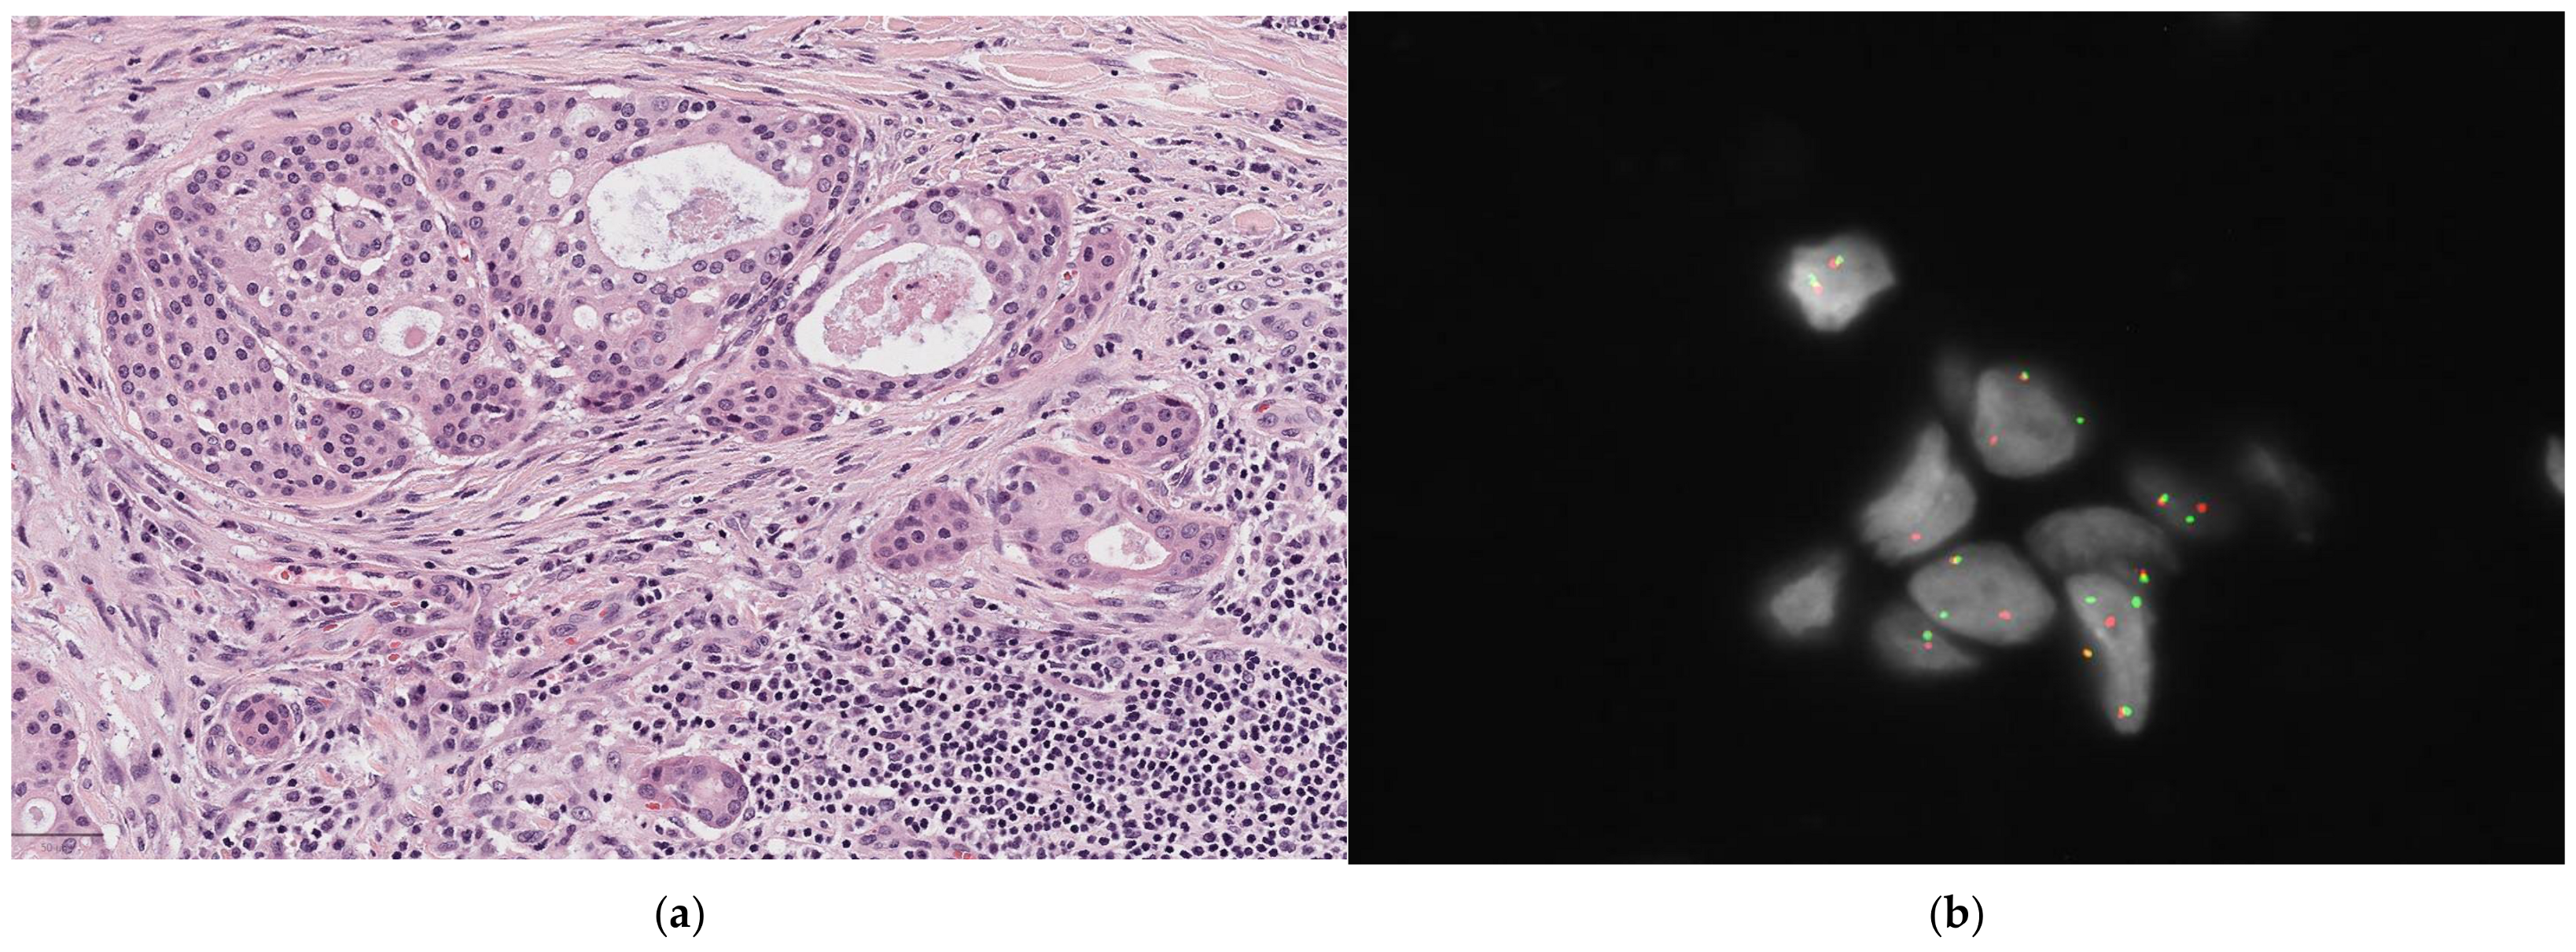

MEC is characterized by the presence of mucous (mucin-producing) cells, intermediate cells, and epidermoid (squamoid) cells. The tumor’s architecture includes both cystic and solid areas, with varying proportions of these cell types. The cystic spaces are partially lined by mucous cells, which have abundant mucinous cytoplasm and nuclei located on the periphery. These cells show intracytoplasmic PAS staining that is resistant to diastase. Extracellular mucin may also be found. Epidermoid (squamoid) and intermediate cells are often the most common type in these tumors. Significant keratinization should be considered an exclusion criterion for the diagnosis of MEC [21,33,34] (Figure 3).

Figure 3.

Mucoepidermoid carcinoma. (a) On H&E (10×), cystic spaces are partly lined by mucous cells. Other cell types include intermediate, squamoid, and partly clear cells; (b) FISH result positive for MAML2 rearrangement.

Several studies have identified specific chromosomal rearrangements, such as CRTC1-MAML2 and CRTC3-MAML2, which have a diagnostic value in both low- and high-grade MECs. These two rearrangements are also associated with improved survival rates [46] [Figure 3b].